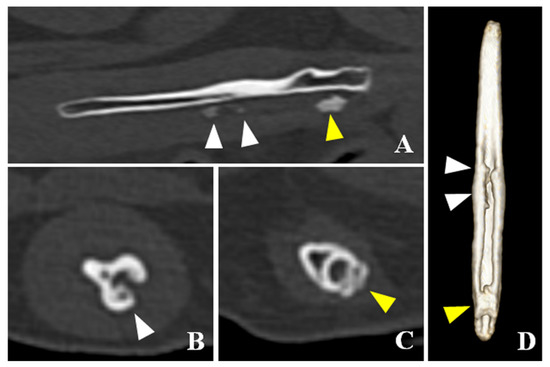

CT detected bladder calculi, urethritis, and proliferation of osseous tissue of the os penis. There was no calculus in the urethra. The normal ureteral groove of the dog was smooth (Figure 2); however, an arch of osseous tissues was formed around the urethra in the caudal portion of the baculum in this case (Figure 3A,C,D). The surface of the urethral groove was nodulous, with proliferation of osseous tissue (Figure 3A,B,D) in the central portion of the os penis. The arch was not formed in this region. In CT angiographic images, portosystemic shunt (left gastro-azygos shunt) was detected.

Figure 3. Computed tomographic images of the os penis in this case. (A) Sagittal plane of the os penis. (B) Transverse plane of the central portion of the os penis. (C) Transverse plane of the caudal portion of the os penis. (D) Ventral view of three-dimensional image of the os penis. In the caudal portion of the os penis, the arch of the osteoid tissues was formed surrounding the urethra (yellow arrowheads). In the central portion of the os penis, the surface of the urethral groove was nodulous due to the proliferation of the osteoid tissue (white arrowheads) but the arch was not Figure 4. Fr catheter confirmed the existence of solid osseous tissue at the base of the os penis, which displaced the urethra dorsally, causing incomplete occlusion of the urethral lumen. The solid osseous tissue was removed by rongeur and ultrasonic disintegrator (SonoCure ™, TOKYO IKEN Co., Ltd, Tokyo, Japan). After its removal, a 6-Fr catheter could pass through this area without any difficulty. Since the 6-Fr catheter could be inserted, the osseous tissue in the middle part of the penis was not immediately removed. The 6-Fr catheter was then placed there for ten days.